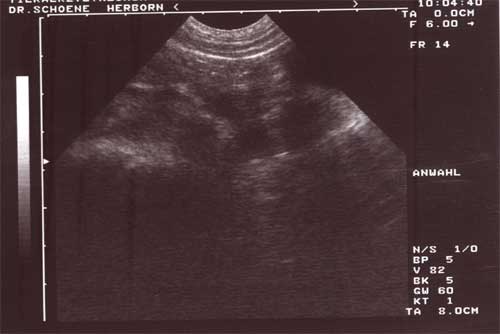

Das Ultraschallergebnis vom 02.01.2002 am Tag 28 nach Decktermin bestätigte die vorhandene Trächtigkeit Jannis:

Hier deutlicher zu erkennen drei Fruchtblasen auf einem Bild.